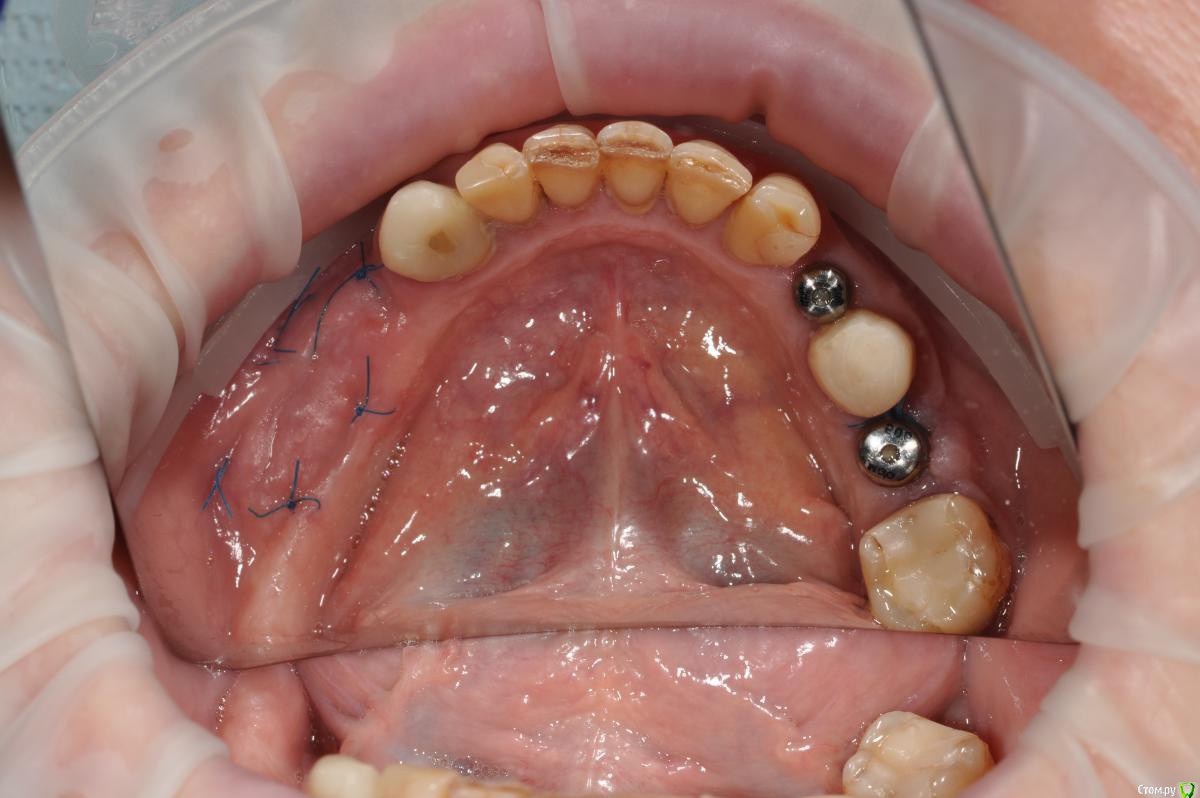

Neilrus Опубликовано 16 ноября, 2018 Поделиться Опубликовано 16 ноября, 2018 Отсеки слизистую и подшей ниже будто сдт собираешься подсадить. С подворотом. Из сом сделай гребень. Клеить и к фдм и к зубам рядом если есть. Надо фото найти... Господа, Как вы решаете вопрос с отсутствием зкпд в полном обьеме.у пациенки жалобы на то что" при поднятии языка, дна полости рта поднимается и нализиет на формирователь десны, соответственно на протезирование я пока не хочу передавать.в течении 3 недель у пациентки выросла шишка под языком в области 3 6 зуба...убрал формирователь и поставил заглушку.Видел у Ильгама как он делал зкпд, не скинете видео? не могу найтии что делать с этой шишкой и как вести пациента? спасибодумаю до надкостницы расщепитесь со стороный переходной, подшейте как можно ниже, а к самой надкостнице полнослойный как можно плотнее пришейте, без фдм будет лучше, их потом, Каппу не забудьте на небо заранее, ибо кусочек будет нормальный.Почти похожий случай, фоткиприкрепил, не судите строго, выкладываюсь редко, прикрепленки было 1,5-2мм и то язычно 2 Ссылка на комментарий

Neilrus Опубликовано 16 ноября, 2018 Поделиться Опубликовано 16 ноября, 2018 (изменено) что-то они в обратно порядке залились..ваще опыта нет (конец вот такой: Изменено 16 ноября, 2018 пользователем Neilrus Ссылка на комментарий

kamranchick Опубликовано 17 ноября, 2018 Автор Поделиться Опубликовано 17 ноября, 2018 думаю до надкостницы расщепитесь со стороный переходной, подшейте как можно ниже, а к самой надкостнице полнослойный как можно плотнее пришейте, без фдм будет лучше, их потом, Каппу не забудьте на небо заранее, ибо кусочек будет нормальный.Почти похожий случай, фоткиприкрепил, не судите строго, выкладываюсь редко, прикрепленки было 1,5-2мм и то язычнону у вас ситуация понятная.... не такая тяжелая, а тут вообще ее нет, даже если бы была язычно 1.5 мм. было бы намного проще. она бы на месте оставалась бы при движении языком туда сюда, в моем случае, любое движение языком это катастрофа Ссылка на комментарий